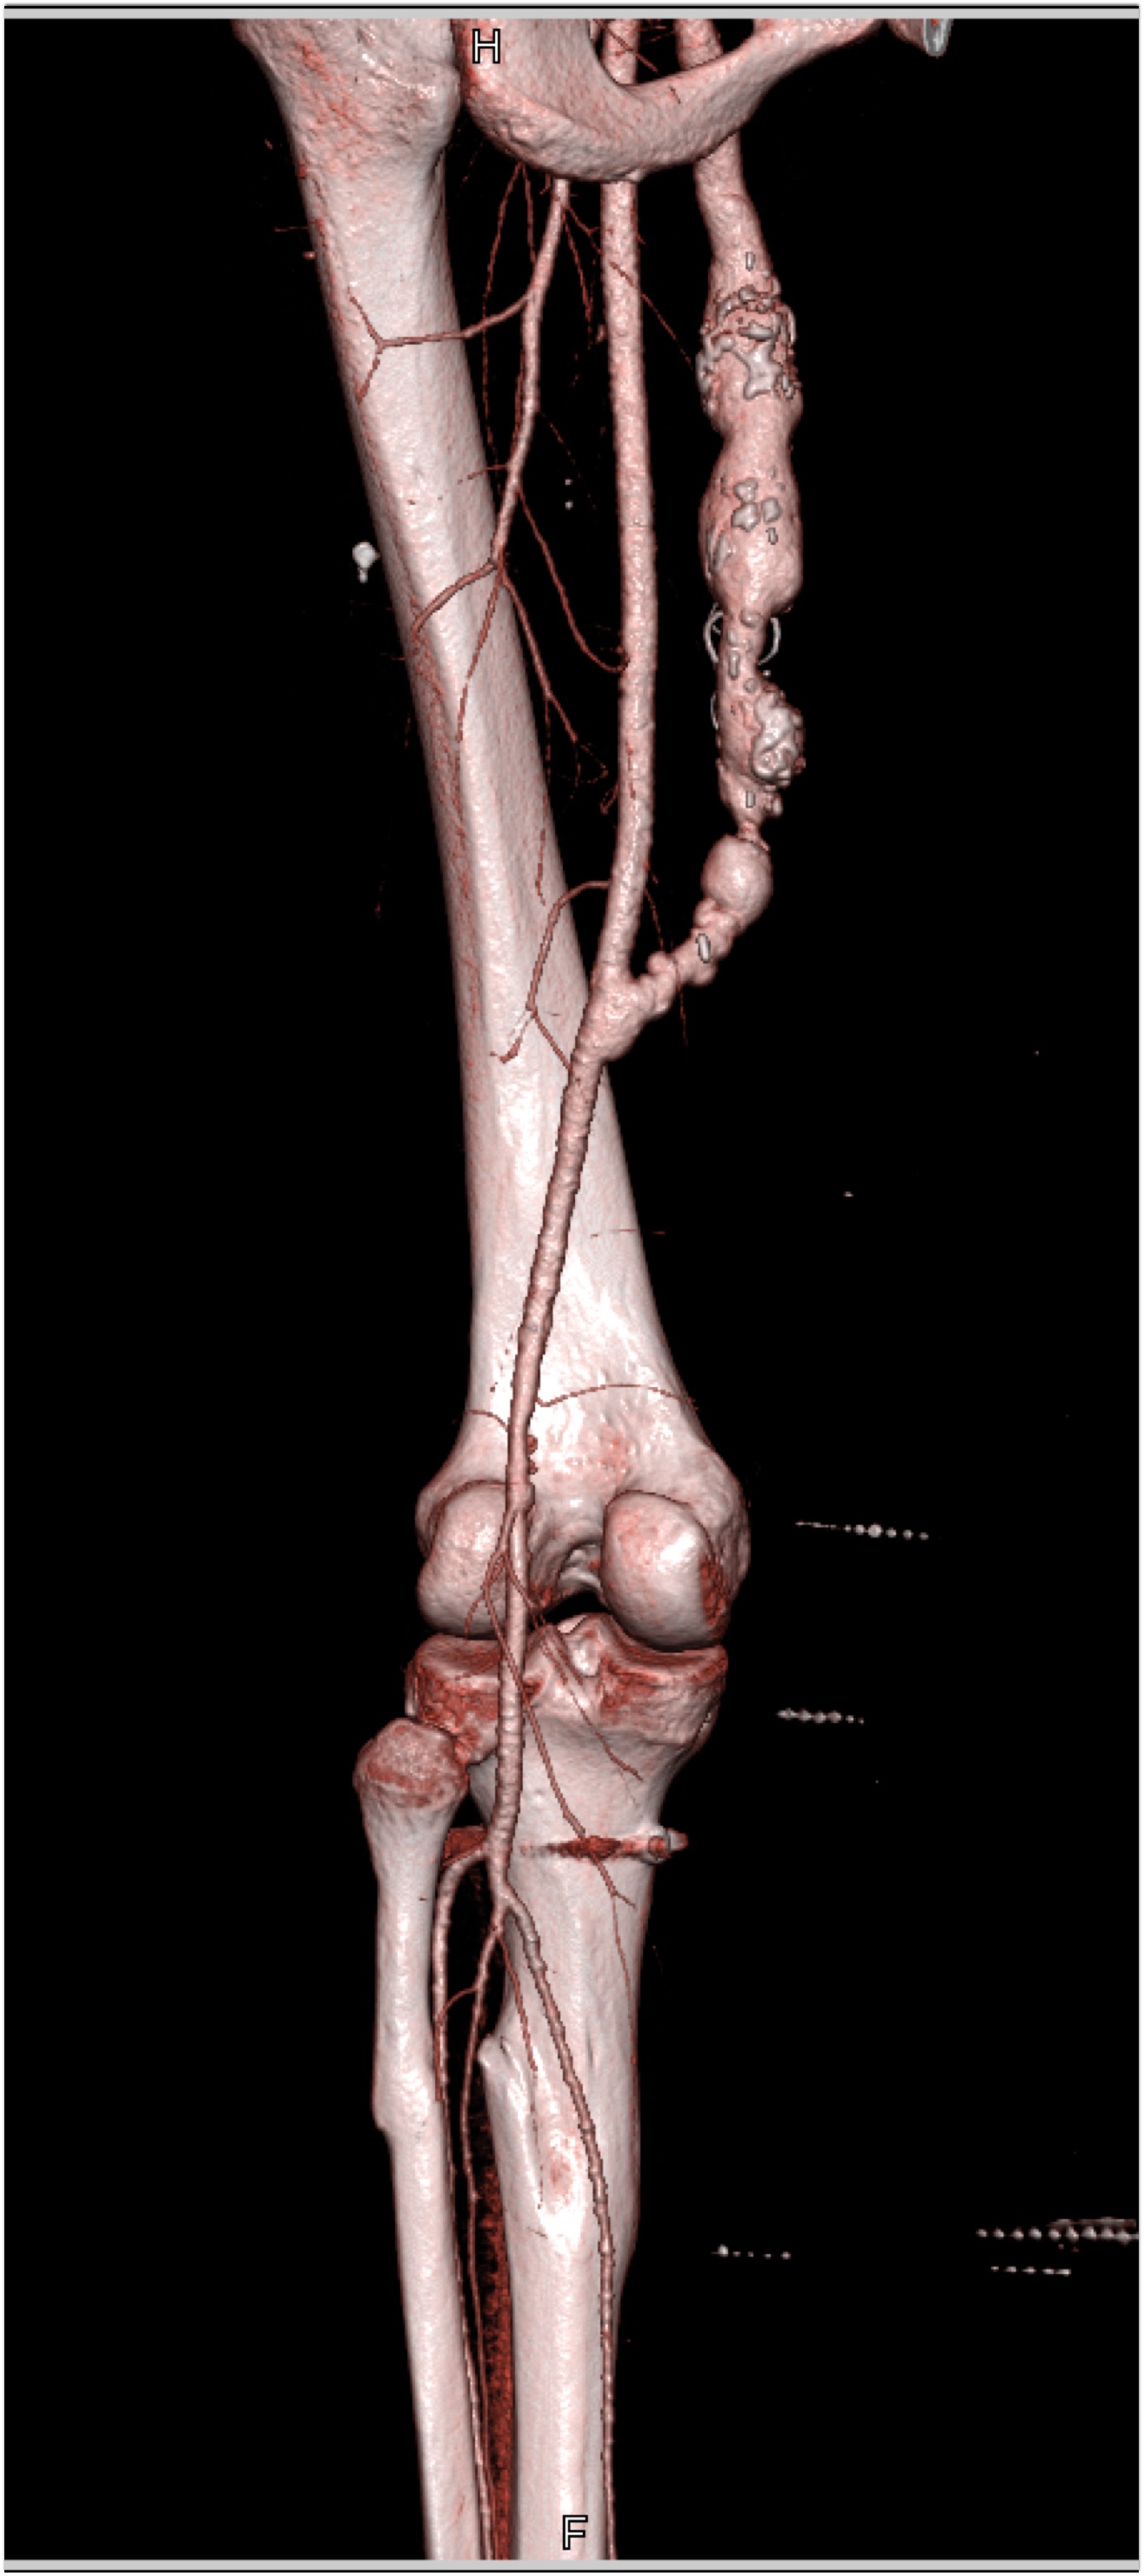

In this patient on dialysis for ESRD the best diagnosis is?

CTisus Quiz   CTisus Quiz

normal bypass graft

AV fistulae with aneurysms

vasculitis

infectious vascular disease